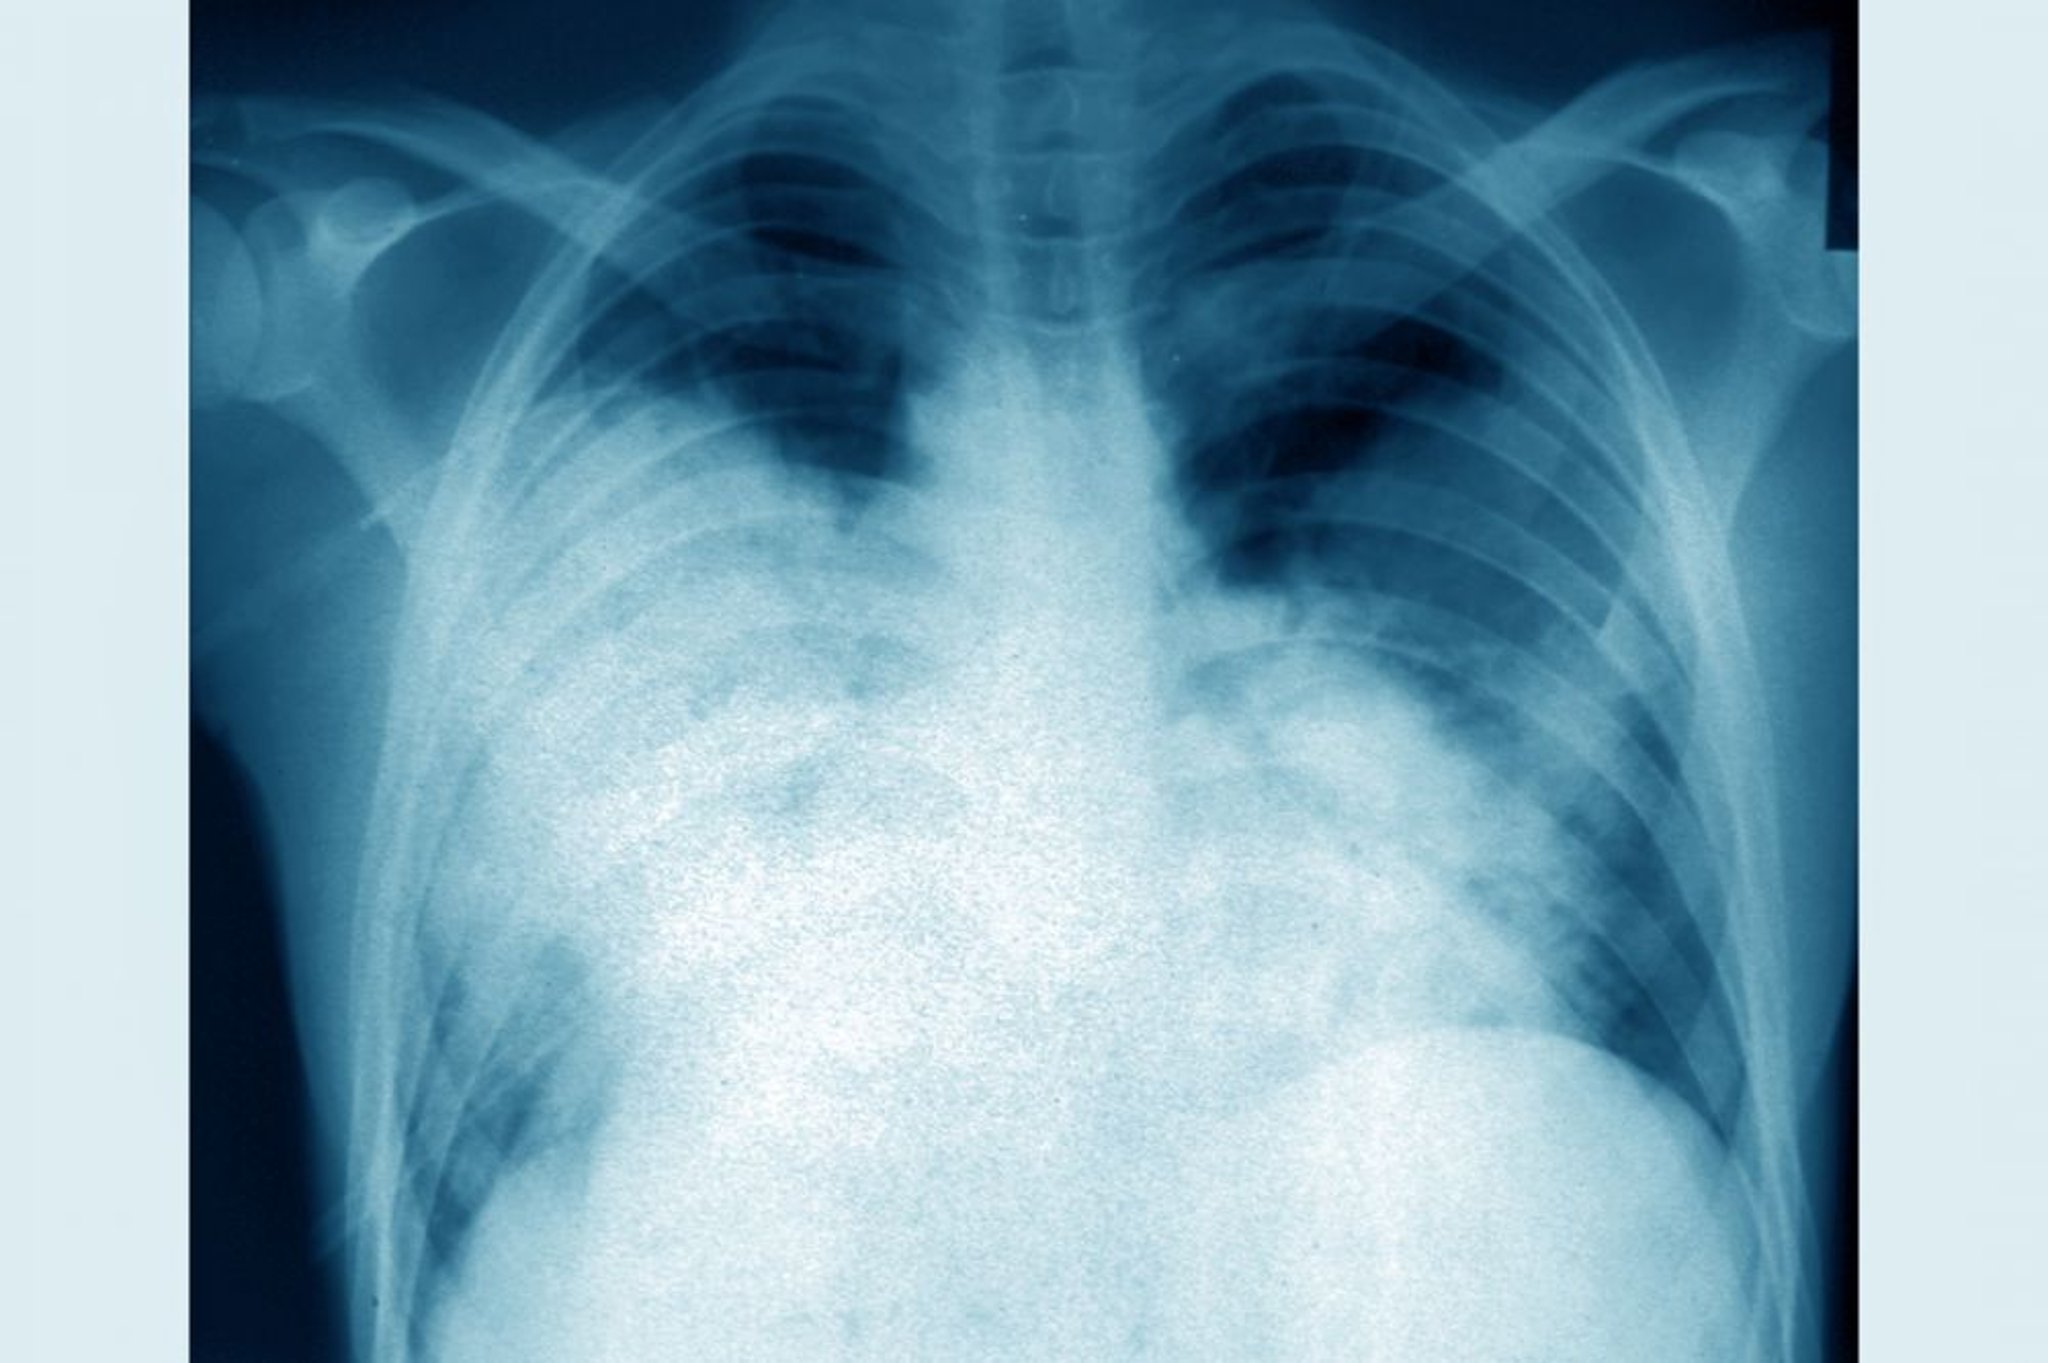

Doença do legionário (radiografia do tórax)

Essa radiografia de tórax frontal mostra pneumonia bilateral aguda (legionelose causada por Legionella pneumophila).